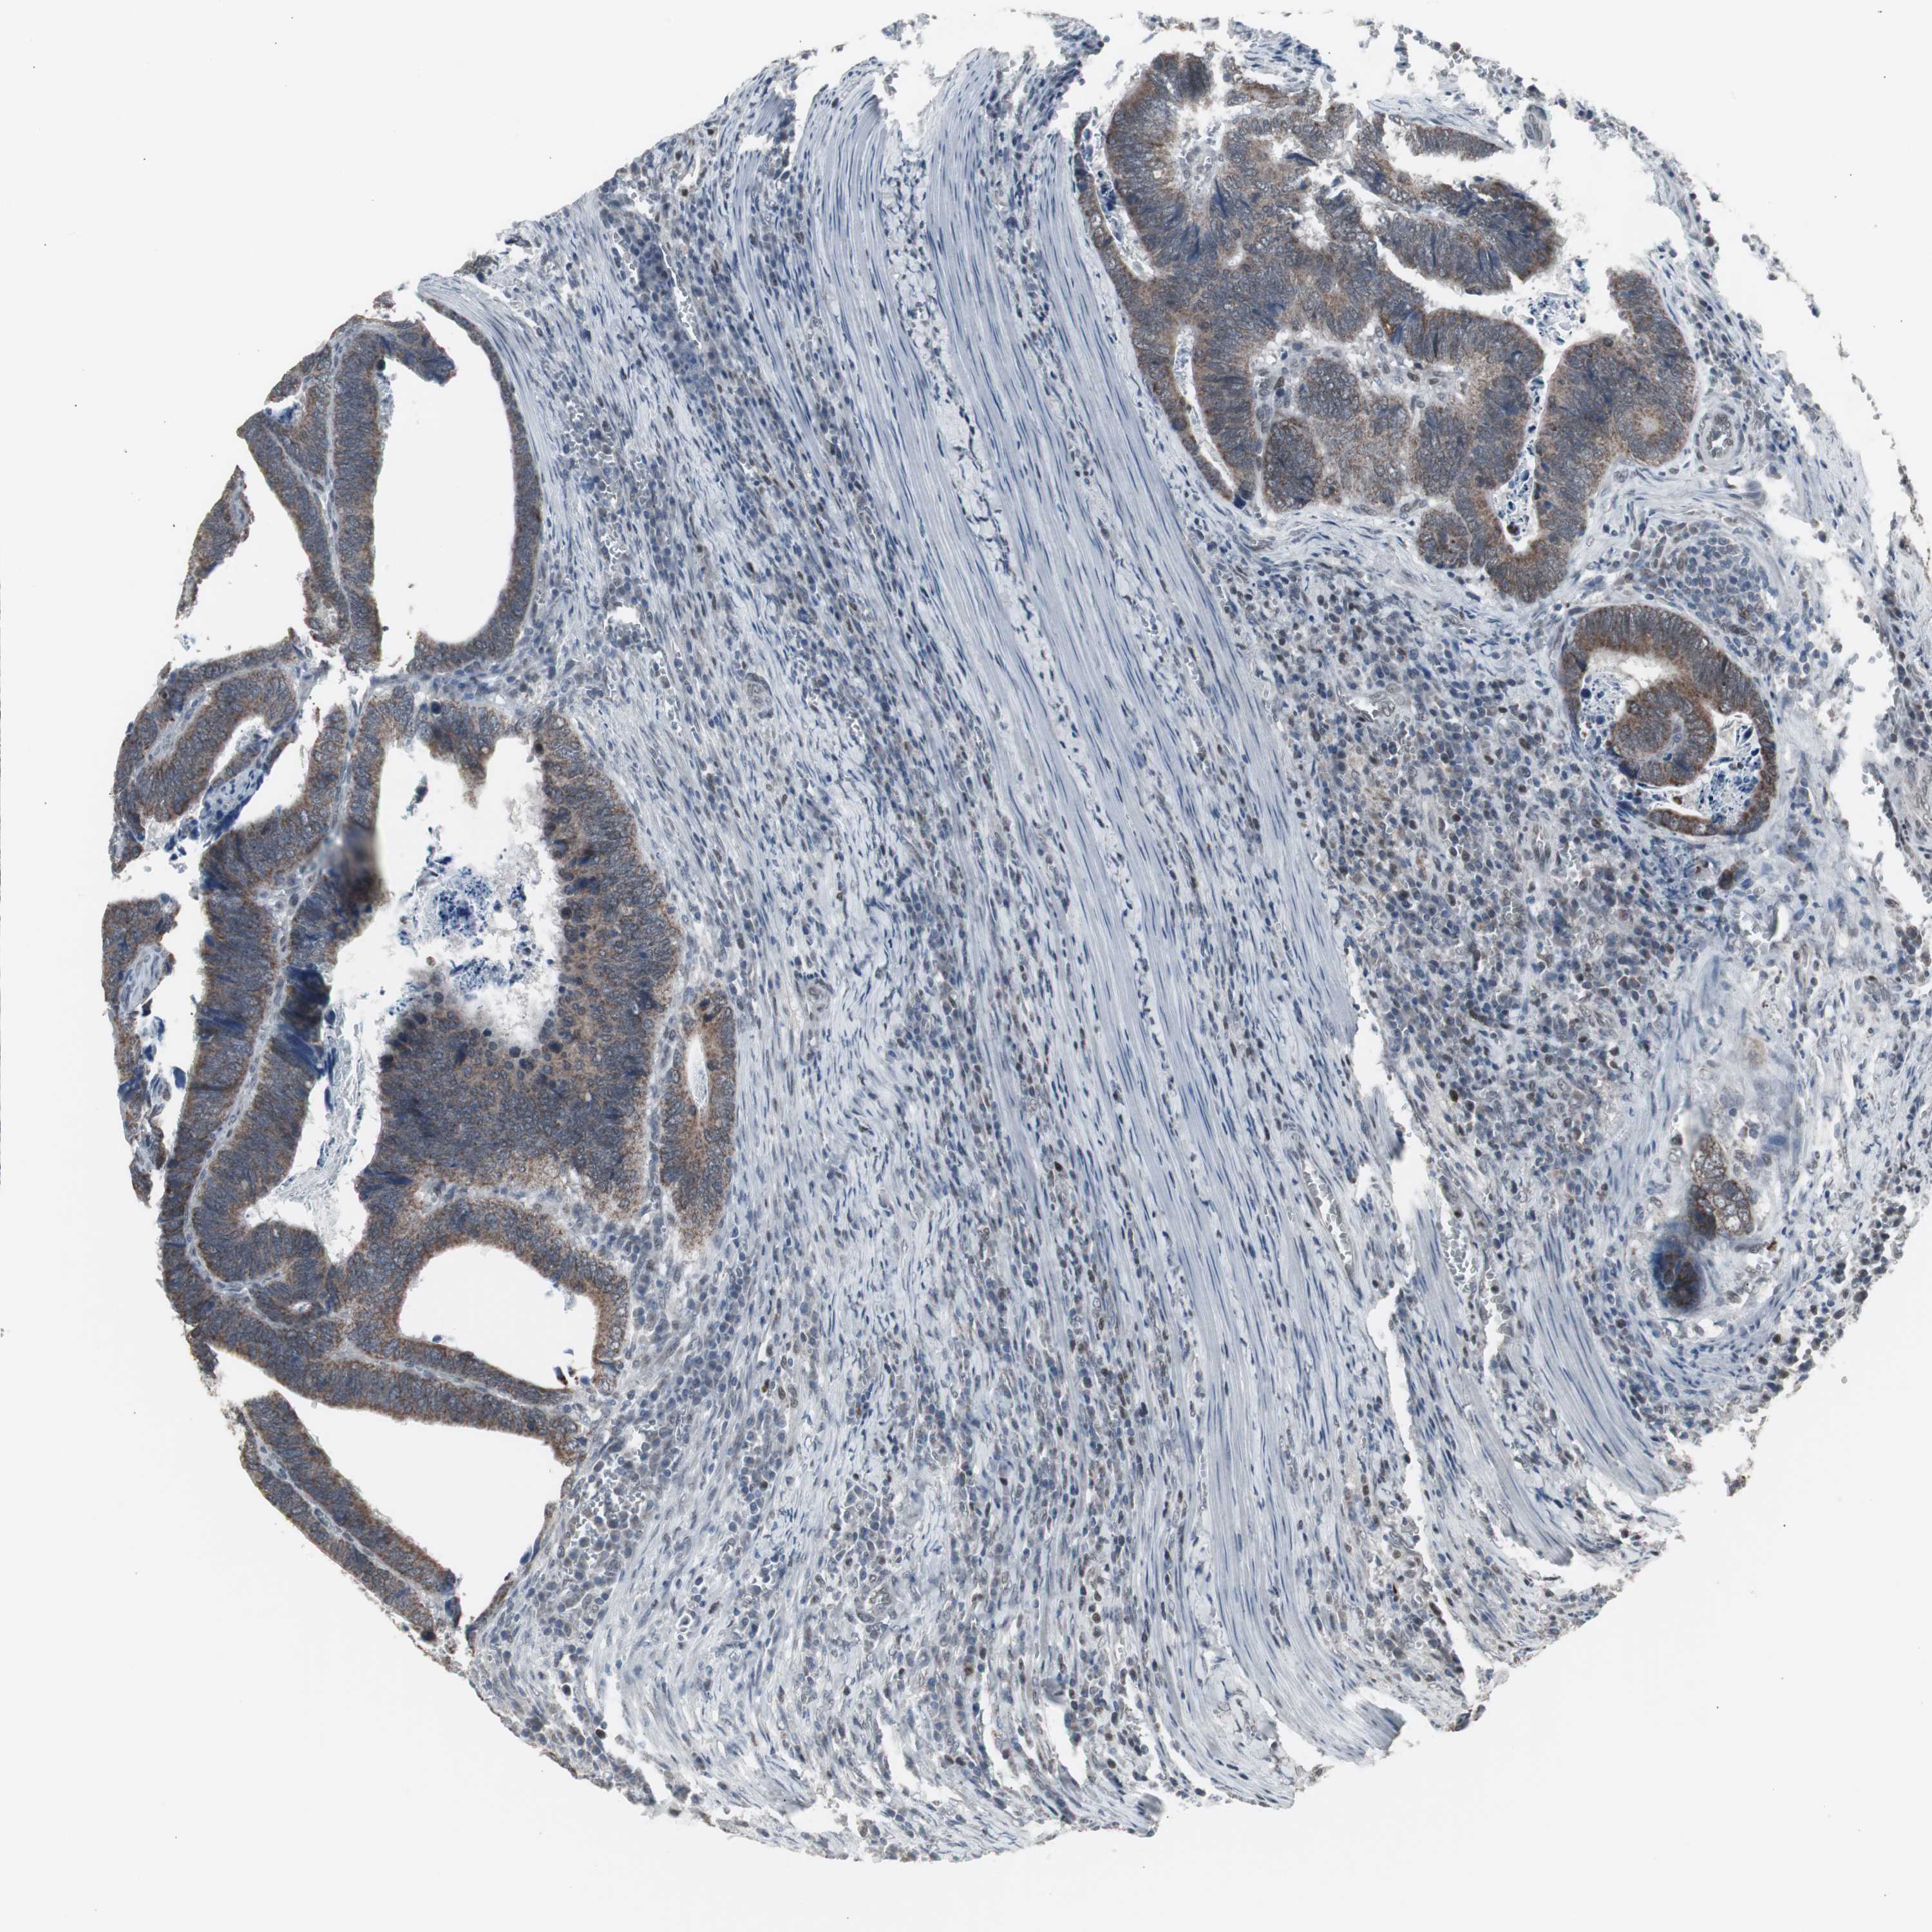

CANCER COLORECTAL CANCER Show tissue menu

Colorectal cancer

Human cancer

Colon adenocarcinoma